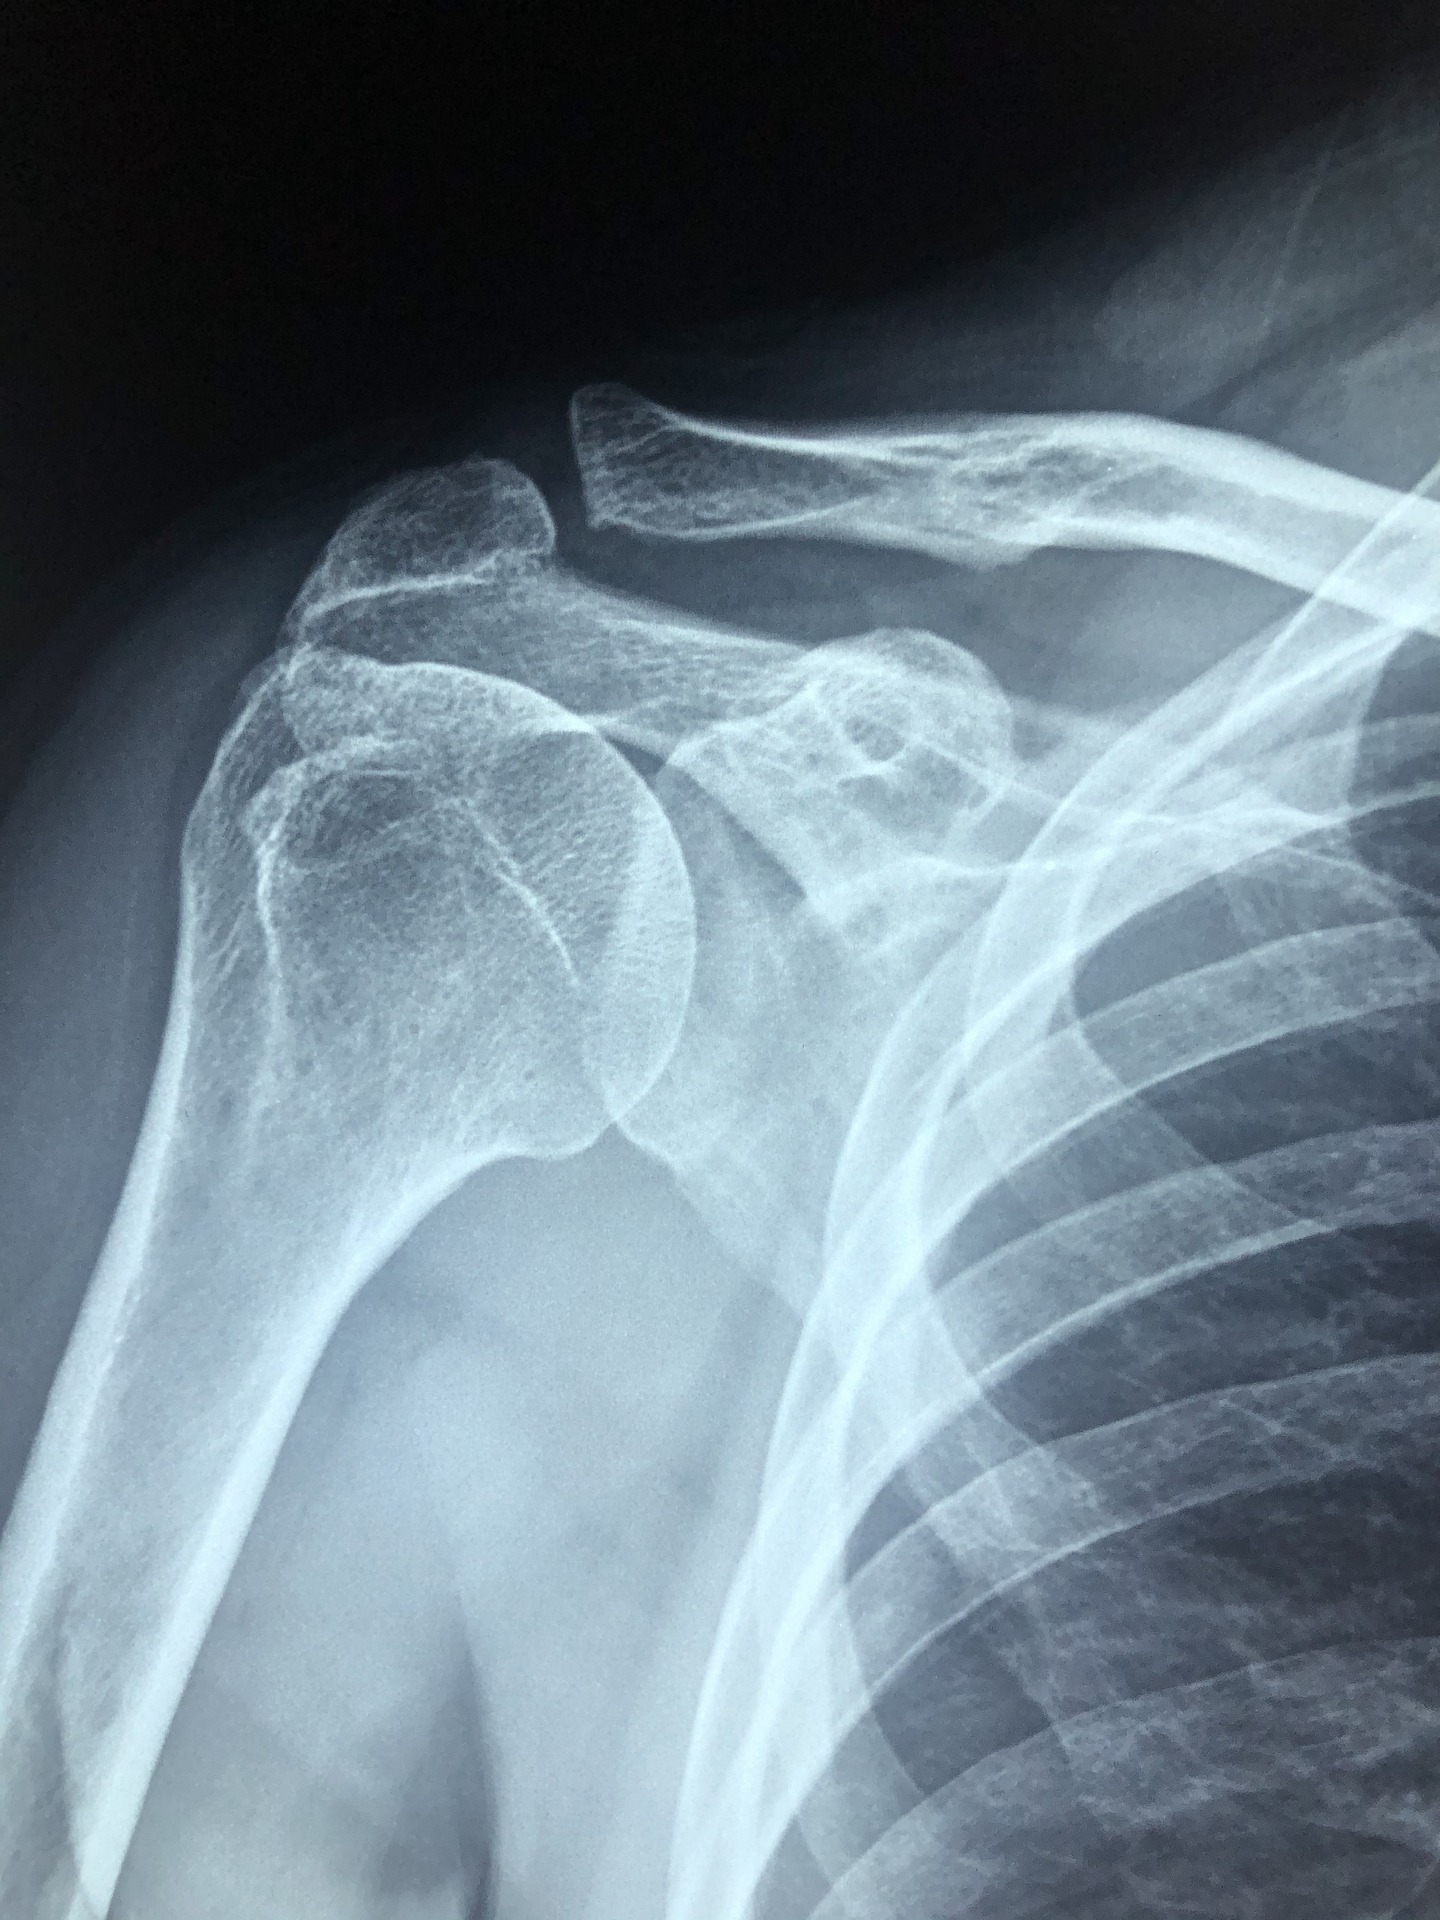

어깨는 상완골, 견갑골, 그리고 쇄골의 세 개의 뼈로 이루어져 있습니다. 어깨는 볼과 소켓 관절입니다. 상완골의 볼, 즉 머리는 견갑골의 얕은 소켓에 맞추어져 있습니다.

팔은 회전근개에 의해 어깨 관절구에 고정됩니다. 회전근개는 상완골 머리 주변을 덮고 있는 4개의 근육 그룹으로 구성된 힘줄입니다. 회전근개는 상완골을 견갑골에 연결하고 팔을 들어 올리고 회전시키는 데 도움이 됩니다.